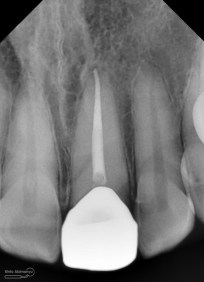

dan ini foto ronsen nya…

Foto radiografis gigi 11 21 22 yang mengalami fraktur

Dari pemeriksaan radiografis lokasi fraktur menyerempet kamar pulpa pada ketiga gigi tersebut… Saya sampaikan kepada pasien bahwa ketiga gigi tersebut memerlukan perawatan saluran akar terlebih dahulu baru kemudian dilanjutkan dengan restorasi indirek… kenapa saya pilih restorasi indirek? Pertimbangannya adalah sisa struktur mahkota gigi yang ada bila hanya di “sambung” dengan restorasi direk dalam jangka panjang rentan mengalami kerusakan, yang kedua pemilihan warna akan lebih maksimal pada kasus ini…. Pasien setuju dengan rencan perawatan yang saya jelaskan…